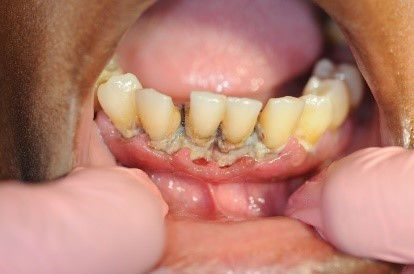

NUG, formerly referred to as acute necrotizing ulcerative gingivitis (ANUG), characteristically presents as a rapid onset of ulcerations of the interdental papilla with gingival bleeding and severe pain. Lesions are typically described as having a “punched out” appearance of the papilla, and the affected tissue appears to be covered with a fibrinous pseudomembrane (see Appendix: Photo- and Radiographs of Periodontal Disease Associated With HIV for images). Biopsy is not initially indicated for diagnosis unless the tissue does not show evidence of healing.

NUP lesions are similar in appearance to NUG lesions; however, NUP lesions extend into and destroy the alveolar bone. Patients with NUP frequently present with exposed bone, gingival recession, and tooth mobility. These clinical signs and symptoms do not necessarily involve the entire periodontium; only localized areas of the tooth-bearing bone and associated soft tissues may be affected. NUP is characterized by rapid destruction of bone that often leads to tooth loss, severe deep jaw pain, widespread soft tissue necrosis, bleeding, and fetid mouth odor. Other signs and symptoms of NUG and NUP include swelling of the regional lymph nodes, fever, and malaise. These clinical findings do not present in all patients and are considered secondary presentations of disease. The presence of NUP may be indicative of severe or worsening immunosuppression Ryder, et al. 2012; Bodhade, et al. 2011.

Appendix: Photo- and Radiographs of Periodontal Disease Associated With HIV

Photographs courtesy of Dr. Gwen Cohen Brown and the Dental Hygiene Department of New York City College of Technology

Figure 2: Patient with necrotizing ulcerative periodontitis (NUP)

Figure 4: Patient with necrotizing ulcerative gingivitis (NUG)